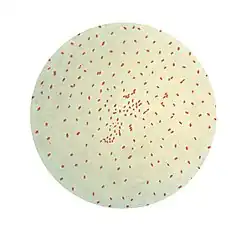

Methods used in laboratory diagnosis include culturing of nasopharyngeal swabs on a nutrient medium (Bordet–Gengou medium), polymerase chain reaction (PCR), direct fluorescent antibody (DFA), and serological methods (e.g. complement fixation test).[34] The bacteria can be recovered from the person only during the first three weeks of illness, rendering culturing and DFA useless after this period. However, PCR may have some limited usefulness for an additional three weeks.